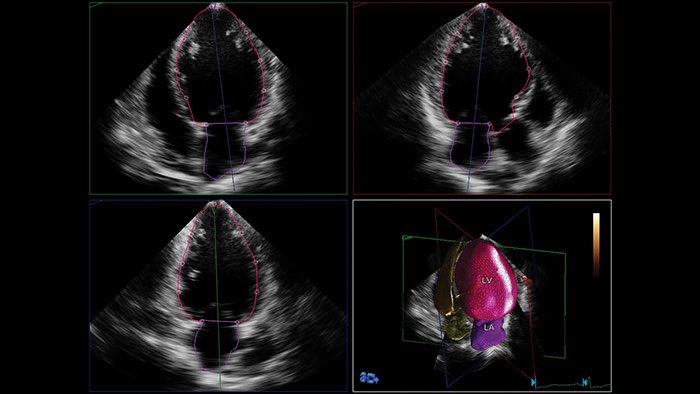

Anatomical Intelligence Ultrasound (AIUS) von Philips, kreiert für eine völlig neue Dimension des Ultraschalls. Mit fortschrittlichen Funktionen für die Organmodellierung, Erstellung von Schnittbildern und zuverlässige Quantifizierung lassen sich Ultraschalluntersuchungen einfach durchführen und besser reproduzieren; gleichzeitig werden aussagekräftige klinische Ergebnisse geliefert, um den wirtschaftlichen und klinischen Herausforderungen der heutigen Gesundheitsumgebung gerecht zu werden.

Zu den Funktionen von AIUS gehören die Automatisierung repetitiver Schritte bis zur kompletten computergesteuerten Analyse von Rohdaten mit minimalen Bedienungsschritten. AIUS kann fortschrittliche Screening-Dokumentation und unterstützte Messungen bereitstellen, daneben gibt es eine Organ- und Strukturerkennung für die automatische Ortskalibration und erweiterte Quantifizierung.